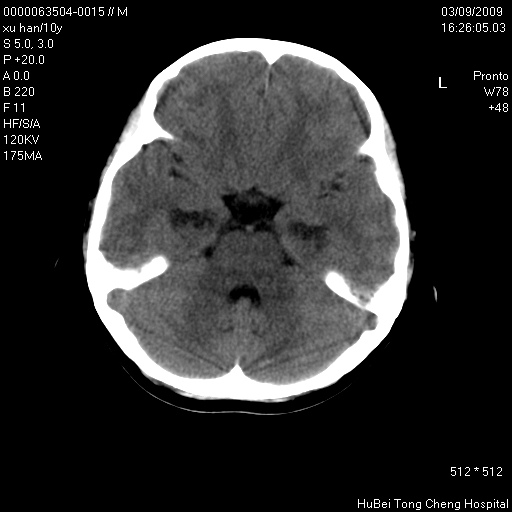

以下是引用道哥在2009-3-9 18:40:00的发言:[br]未见明显异常,必要时mr(dwi)成像。

以下是引用余辉在2009-3-10 11:01:00的发言:[br]考虑双侧海马急性缺氧性损伤